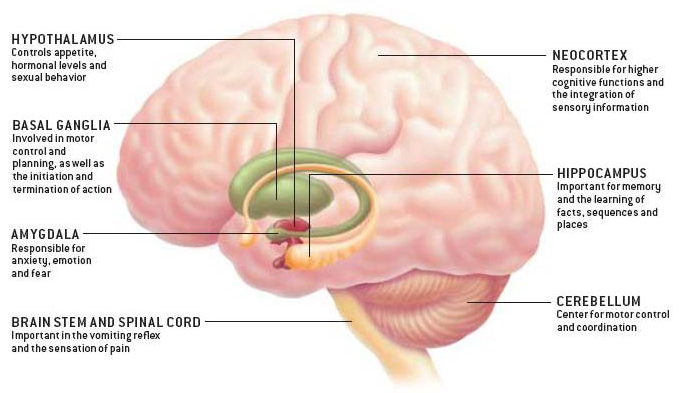

1. Promotes Neurogenesis

Recent studies indicate that a natural cannabinoid of cannabis, specifically CBD, increases adult neurogenesis. R

Cannabidiol reduced Aβ-induced neuroinflammation and promotes hippocampal neurogenesis through PPARγ involvement. R

Repeated administration of CBD increased hippocampal progenitor proliferation and neurogenesis in wild-type mice. R

In mice, chronic THC exposure increased BDNF in the hippocampus, but not the frontal lobe. R

3. Protects the Brain

Acute and chronic administration of cannabidiol increases mitochondrial complex and creatine kinase activity in the rat brain. R

CBD produced significantly better intracranial pressure/cerebral perfusion pressure control without jeopardizing blood pressure. R

4. Helps with Anxiety

CBD was shown to reduce anxiety in patients with social anxiety disorder (by inducing activity in limbic and paralimbic brain areas). R R

It also helped with public speaking induced anxiety. R

CBD has anxiolytic and possibly antipsychotic properties. CBD was associated with activation in right temporal cortex during auditory processing. During visual processing, CBD increased activation relative to placebo in the right occipital lobe, with maxima in the middle and inferior occipital gyri, the lingual gyrus, and cuneus. R

5. Helps with Stress

Proper endocannabinoid signaling modulates the HPA axis. R RR

Stress-induced downregulation of hippocampal eCB signaling. R

What is interesting (just like microdosing yourself to stress) is that repeated exposure to the same stress can sensitize CB1 receptor signaling, resulting in dampening of the stress response. R

- CB1 receptor-endocannabinoid signaling is activated by stress and functions to buffer or dampen the behavioral and endocrine effects of acute stress. R

- chronic stress downregulated CB1 receptor expression and significantly reduced the content of the endocannabinoid 2-arachidonylglycerol within the hippocampus. R